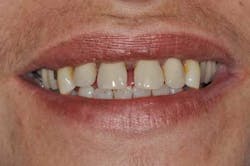

Figs. 8a, b, c, and d: Final results

Figs. 9a, b, and c: Two years’ postop. Note the patient’s commitment to maintaining an optimal oral hygiene